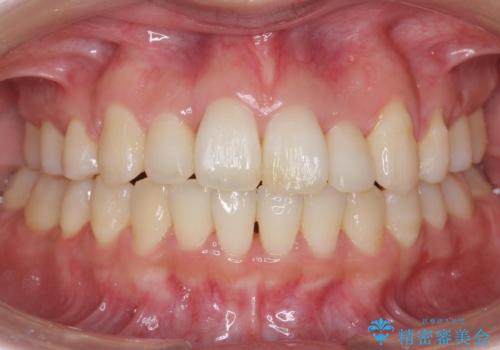

- 歯並びを気にして来院。

前歯は重度のがたつき、また奥歯はすれ違っていました。

治療は3年以上かかりそうと説明しましたが、2年台で終わらせることができました。

上下左右4本抜歯の可能性を説明していましたが、実際は上顎2本の小臼歯抜歯で済みました。